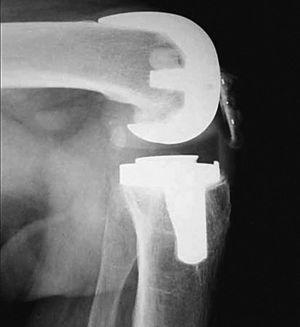

A los 4 meses la movilidad empeoró a 0-55° y el dolor anterior de rodilla provocaba la necesidad de medicación analgésica diaria. Los estudios radiológicos fueron normales y se descartó la infección. Comenzó a desarrollar un síndrome de patela baja; realizó tratamiento rehabilitador sin resultado satisfactorio. Se realizó entonces un desbridamiento artroscópico que confirmó la presencia de artrofibrosis, por lo que se procedió a la liberación exhaustiva de las adherencias y tejido fibroso intraarticular; la rótula mostró un defecto condral grado II de Outerbridge. Los cultivos tomados fueron negativos para infección. El arco de movilidad mejoró hasta llegar a 0-80°. Sin embargo, un año después, el dolor y la rigidez habían aumentado, presentando cierta incapacidad para subir y bajar escaleras; precisaba bastones y medicación analgésica. La KSS fue 43 + 30. El tendón rotuliano se retrajo un 15% comparando radiografías previas y el polo distal de la rótula tocaba el labio anterior del polietileno (fig. 2). El índice Insall-Salvati fue 0,91, Blackburne 0,63 y Caton 0,64. Las pruebas de infección continuaban siendo negativas. Las radiografías mostraban un dudoso aflojamiento del platillo tibial, que no se confirmó posteriormente.

Figura 2. Visión intraoperatoria del roce del polietileno con el polo inferior de la rótula.